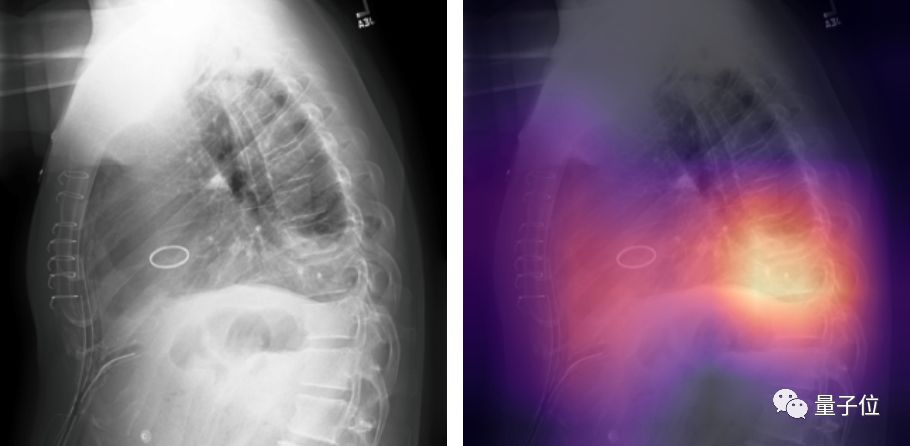

最近,吴恩达的斯坦福团队发布了一个叫做CheXpert大型数据集,论文中选了AAAI 2019

它包含了224,316张标注好的胸部X光片,以及放射科医师为每张胸片写的病理报告。

团队便是用这个数据集做Benchmark,举行了一场5种疾病的识别比赛。

用500张胸片的测试集来比,这个模型在心脏肥大、肺水肿以及胸腔积液这三项上,超越了前面提到的“另外3位人类医师”

若以粗暴的五局三胜为规则,AI已经赢了。